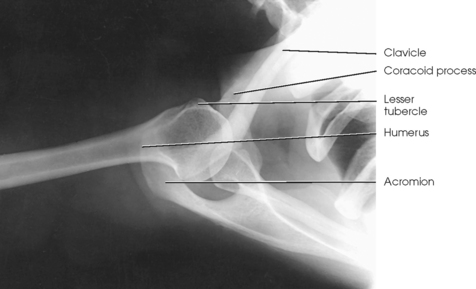

The shoulder girdle is formed by two bones—the clavicle and scapula. The function of these bones is to connect the upper limb to the trunk. Although the alignment of these two bones is considered a girdle, it is incomplete in front and in back. The girdle is completed in front by the sternum, which articulates with the medial end of the clavicle. The scapulae are widely separated in the back. The proximal portion of the humerus is part of the upper limb and not the shoulder girdle proper; however, because the proximal humerus is included in the shoulder joint, its anatomy is considered with that of the shoulder girdle (Figs. 5-1 and 5-2).

The clavicle, classified as a long bone, has a body and two articular extremities (see Fig. 5-1). The clavicle lies in a horizontal oblique plane just above the first rib and forms the anterior part of the shoulder girdle. The lateral aspect is termed the acromial extremity, and it articulates with the acromion process of the scapula. The medial aspect, termed the sternal extremity, articulates with the manubrium of the sternum and the first costal cartilage. The clavicle, which serves as a fulcrum for the movements of the arm, is doubly curved for strength. The curvature is more acute in males than in females.

The proximal end of the humerus consists of a head, an anatomic neck, two prominent processes called the greater and lesser tubercles, and the surgical neck (Fig. 5-5). The head is large, smooth, and rounded, and it lies in an oblique plane on the superomedial side of the humerus. Just below the head, lying in the same oblique plane, is the narrow, constricted anatomic neck. The constriction of the body just below the tubercles is called the surgical neck, which is the site of many fractures.

The lesser tubercle is situated on the anterior surface of the bone, immediately below the anatomic neck (Figs. 5-6 and 5-7; see Fig. 5-5). The tendon of the subscapular muscle inserts at the lesser tubercle. The greater tubercle is located on the lateral surface of the bone, just below the anatomic neck, and is separated from the lesser tubercle by a deep depression called the intertubercular (bicipital) groove. The superior surface of the greater tubercle slopes posteriorly at an angle of approximately 25 degrees and has three flattened impressions for muscle insertions. The anterior impression is the highest of the three and affords attachment to the tendon of the supraspinatus muscle. The middle impression is the point of insertion of the infraspinatus muscle. The tendon of the upper fibers of the teres minor muscle inserts at the posterior impression (the lower fibers insert into the body of the bone immediately below this point).